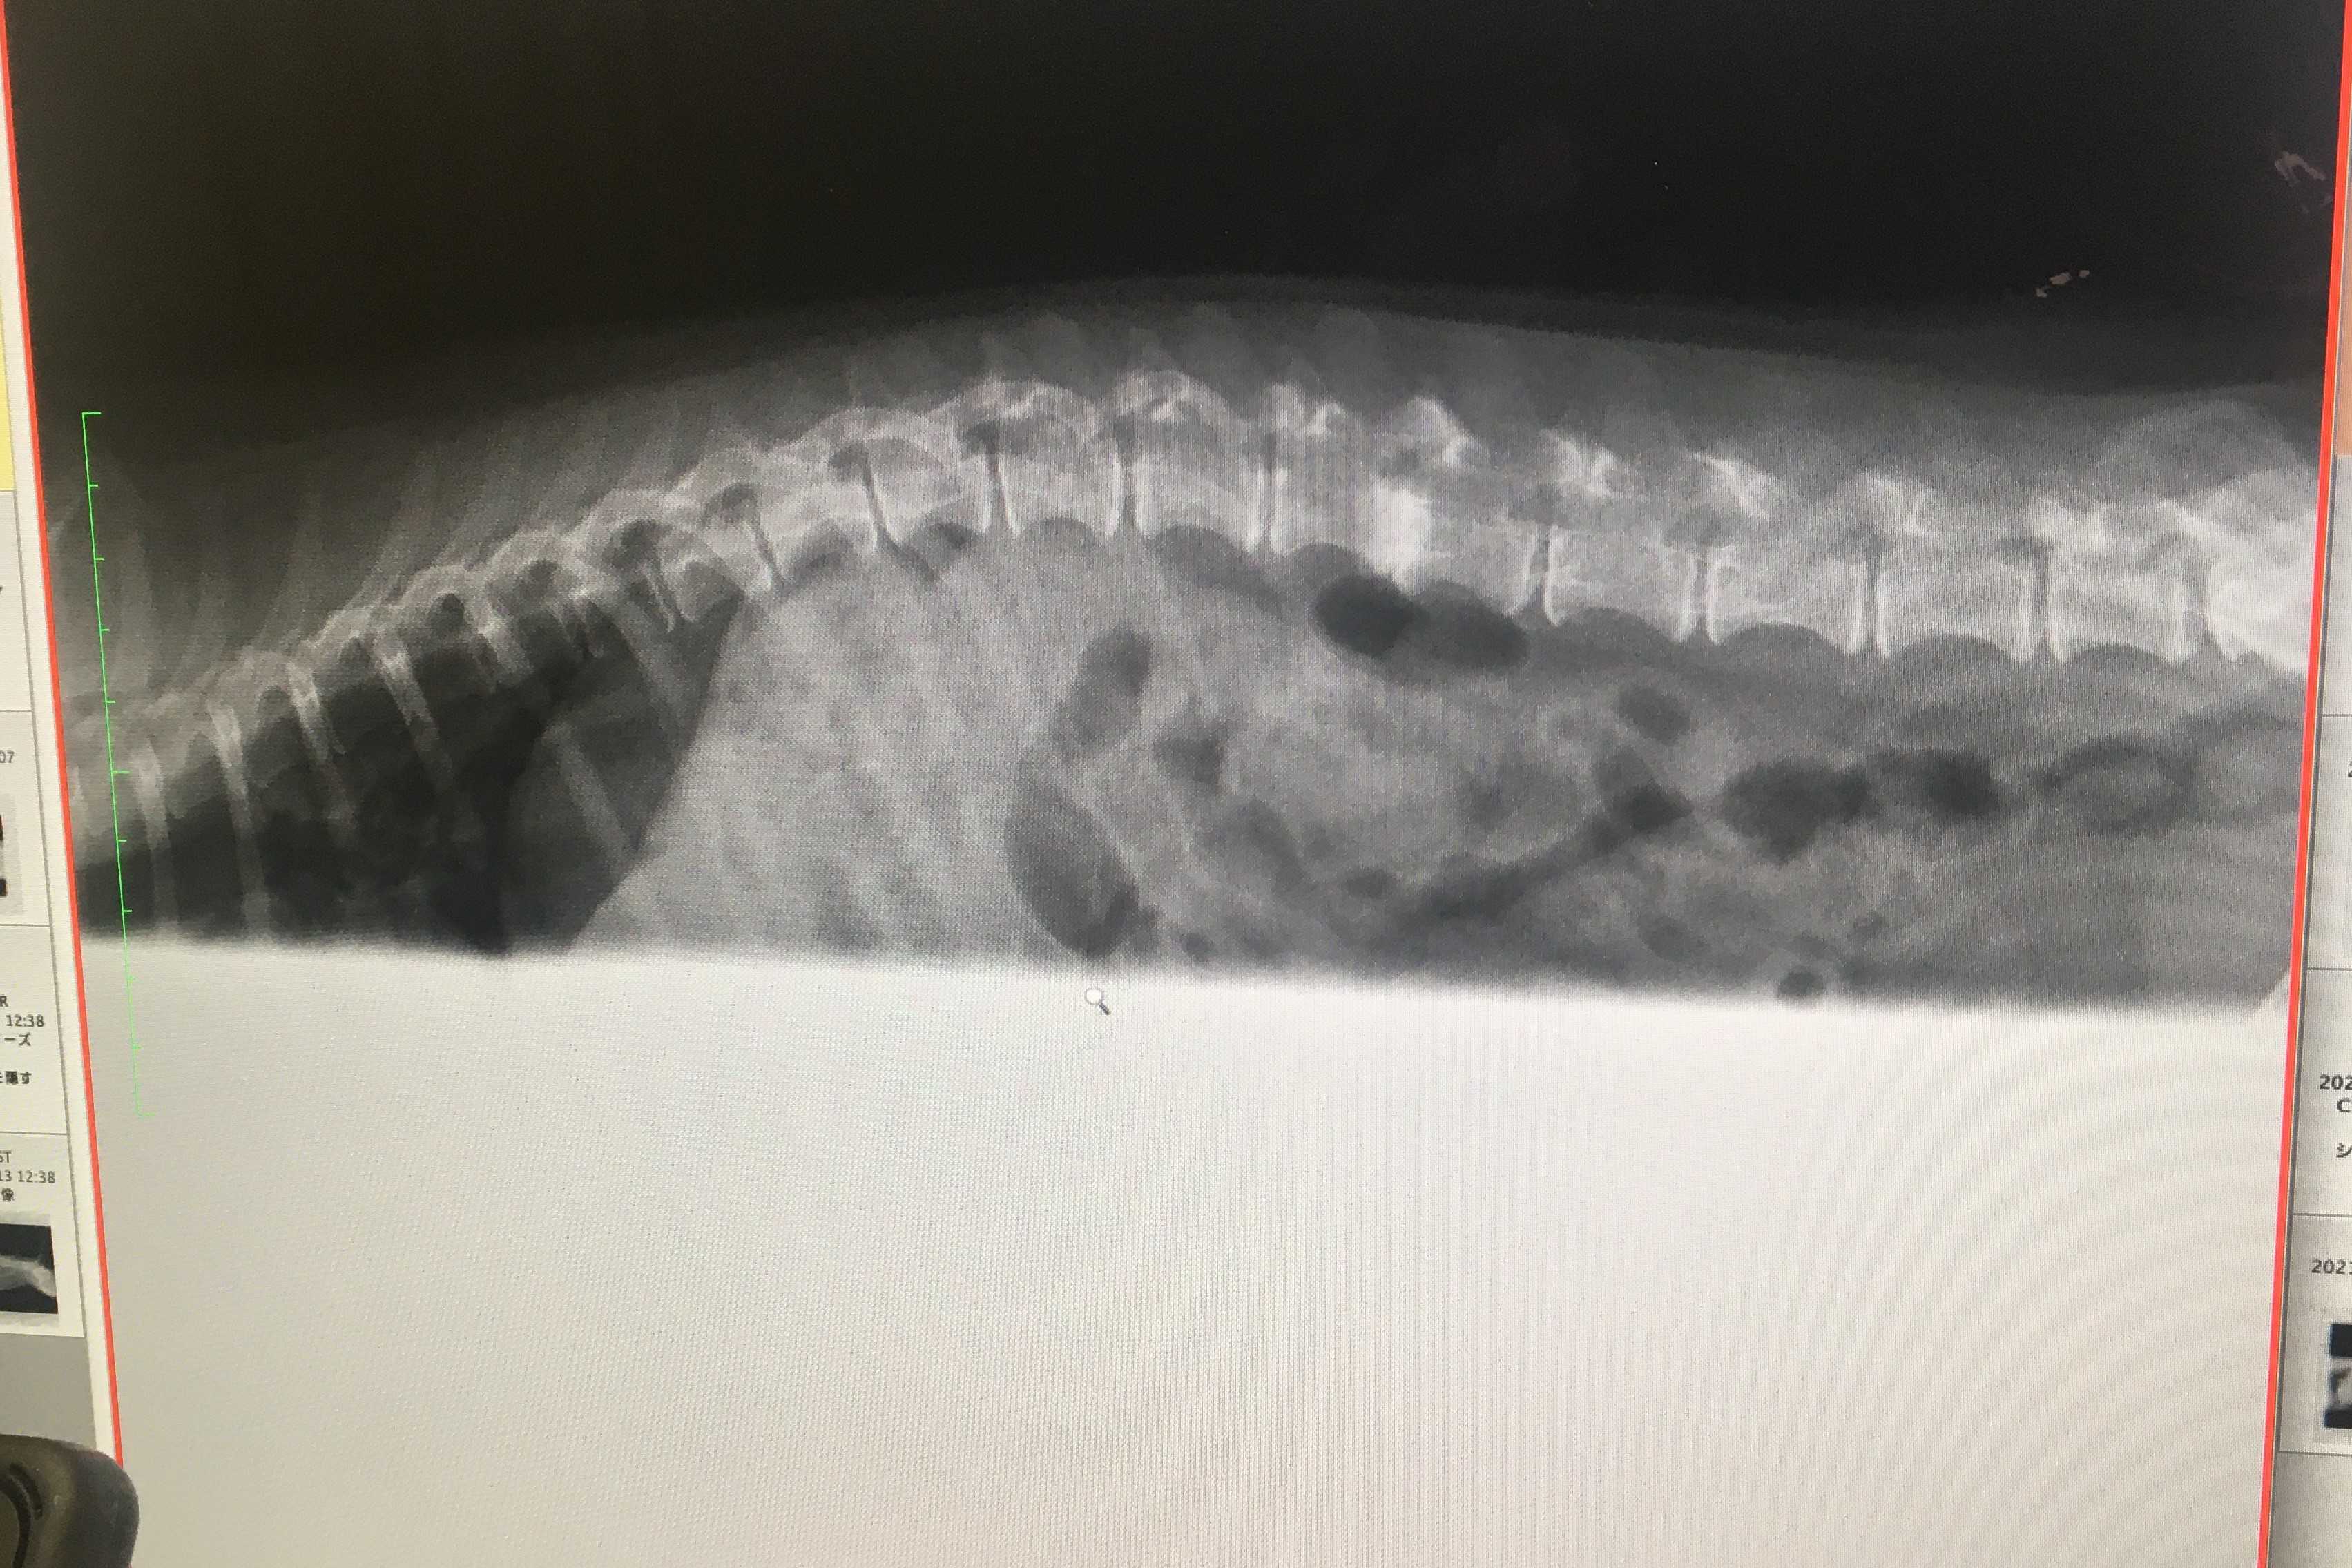

レントゲンの画像がありますので苦手な方はご遠慮ください

こちら2月に撮ったレントゲンですね

で、これは今回撮ったものです

異常は無さそうですね

2月のレントゲンもそうなんですけど、白くなってるところは何ですか?

これはヘルニアの痕ですね

症状が出ないまま治ってしまったのでしょう

軟骨部分がすり減った状態です

変形性脊椎症ではないのですか

こちらは違いますね